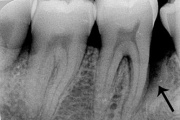

Agressiivne parodontiit

Seda parodontiidi vormi esineb umbes1%-l elanikkonnast. On haiguse kiiresti progresseeruv vorm, mille puhul patsiendid kaotavad kõik hambad enne30-35. eluaastat. Tavaliselt haigestutakse piimahammaste lõikumise ja puberteedi vahele jääval perioodil. Jagunemine:- lokaliseeritud agressiivne vorm- Loe edasi »